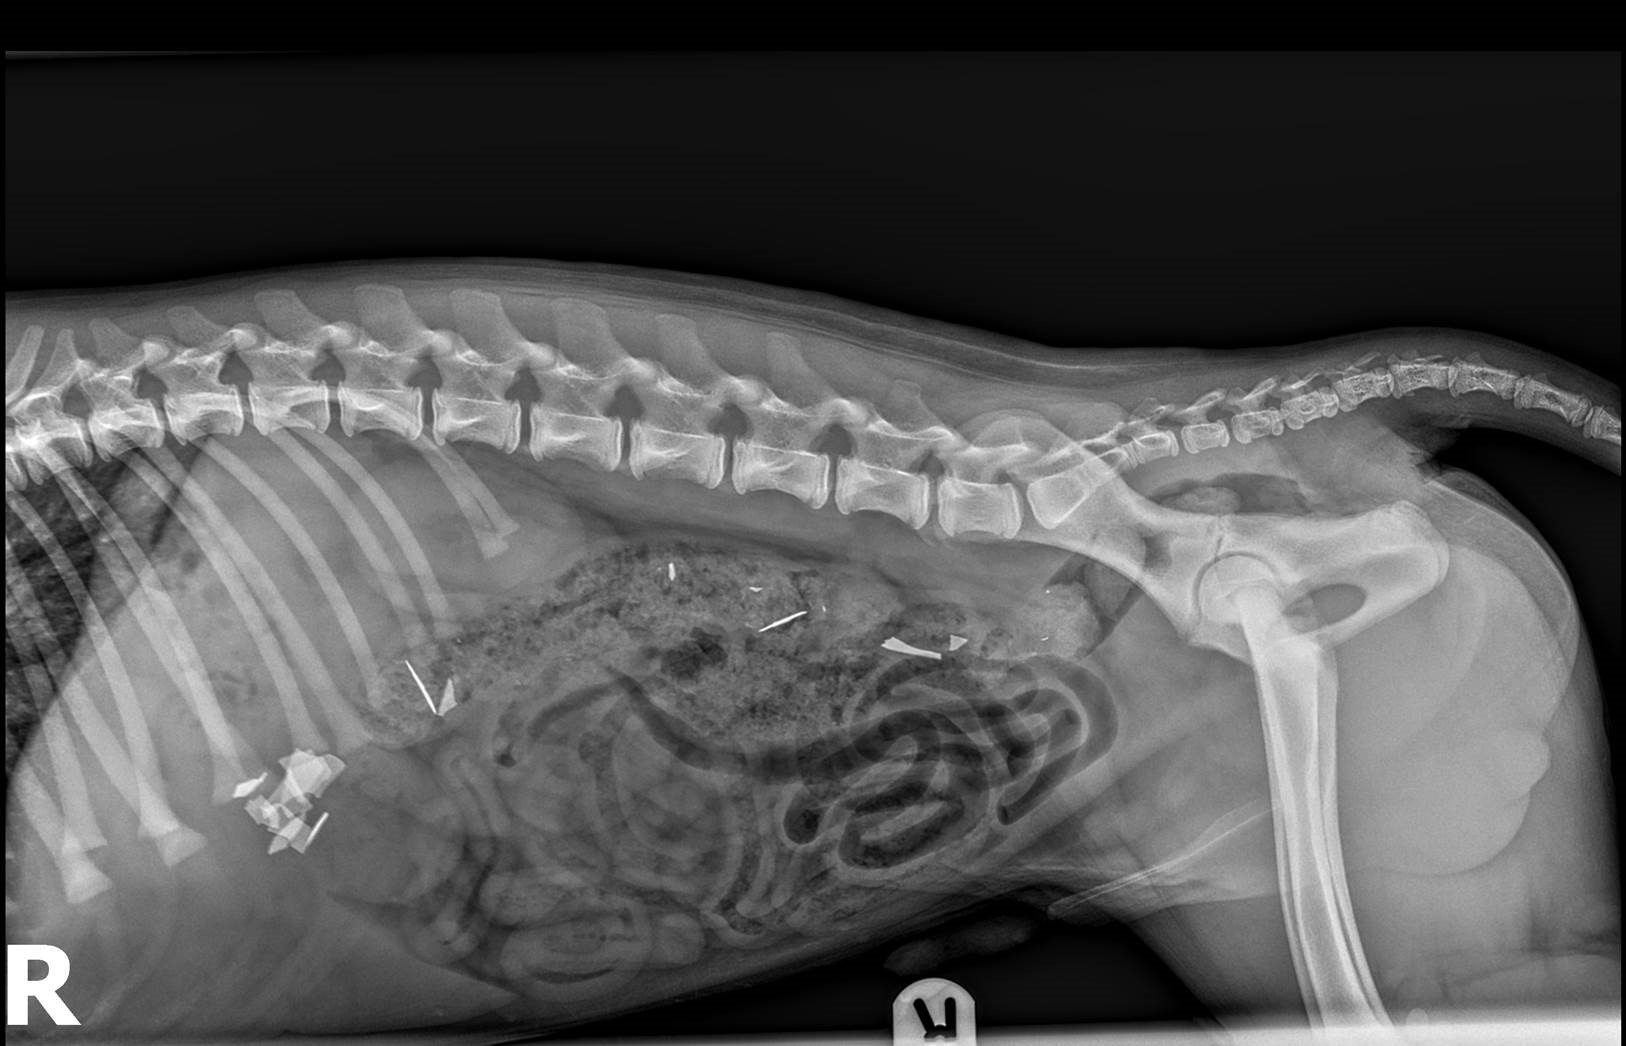

This chap ingested 28 safety razor blades. If a razor blade passes the stomach and duodenum, then it usually passes through the lower gastrointestinal tract. It passed throughout the rest of the bowel without complication. Multiple metallic foreign bodies are noted in the upper abdomen. Multiple radiopaque foreign bodies are demonstrated throughout the abdomen, consistent with ingested razor blades. Therefore, a computed tomography (ct) was requested, which. The case demonstrates that after eventlessly passing through the oesophagus even very sharp foreign bodies such as razor blades can exit. It is located on the right side of the abdomen and is therefore beyond the stomach. Therefore, a computed tomography (ct) was requested, which revealed two metal foreign bodies, (razor blades). We report a case of accidental ingestion of a razor blade in a chronic alcoholic who presented with hematemesis after an esophageal.

From www.veterinary-practice.com

Close shave for puppy who swallowed razor blades Veterinary Practice Razor Blades X Ray Therefore, a computed tomography (ct) was requested, which. We report a case of accidental ingestion of a razor blade in a chronic alcoholic who presented with hematemesis after an esophageal. Multiple metallic foreign bodies are noted in the upper abdomen. If a razor blade passes the stomach and duodenum, then it usually passes through the lower gastrointestinal tract. It passed. Razor Blades X Ray.